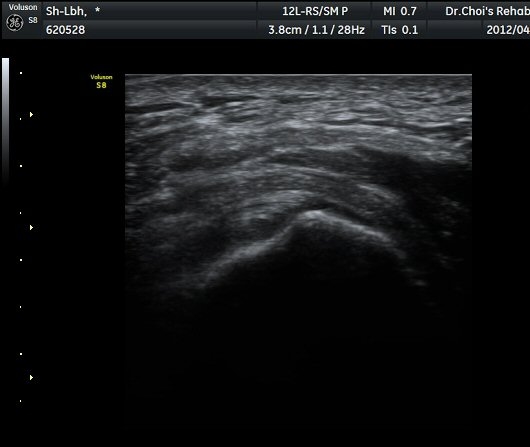

´ëÀüÀÚ(gtreater trochanter) ¾ÕºÎºÐ Ⱦ´Ü¸é °Ë»ç¿¡¼­ ´ëÀüÀÚ Ç¥Ãþ¿¡ ¼ÒµÐ±ÙÀÌ °í¿¡ÄÚ ¼¶À¯¾ç ¸ð¾çÀ¸·Î °üÂûµÇ°í ¼ÒµÐ±Ù°ú Àå°æÀÎ´ë »çÀÌ¿¡ ¾à 2mm µÎ²²ÀÇ Á¤¾×³¶ ºÎÁ¾ÀÌ °üÂûµÈ´Ù(±×¸² 1, ³ë¶õ»ö È­»ìÇ¥) . ŽÃËÀÚ¸¦ µÚÂÊÀ¸·Î À̵¿ÇÏ¿© Áߵб٠ÈûÁÙÀÌ °üÂûµÇ°í Áߵб٠ÈûÁÙ ºÎÂøºÎ ÀϺο¡ ¹«¿¡ÄÚ ¿¬°á¼º ¼Ò½ÇÀÌ °üÂûµÇ°í ±× Ç¥Ãþ¿¡µµ Á¡¾×³¶ÀÇ ºÎÁ¾ÀÌ °üÂûµÈ´Ù(±×¸² 2). ȯÀÚÀÇ µÚÂÊ¿¡¼­ ÃÊÀ½ÆÄ À¯µµÇÏ ÁÖ»çÄ¡·á¸¦ À§ÇØ ºñ½ºµëÇÑ È¾´Ü¸é°Ë»ç¿¡¼­ ´ëµÐ±Ù

ÃÊÀ½ÆÄ À¯µµÇÏ Á¡¾×³¶³» ÁÖ»çÄ¡·á(÷ºÎ µ¿¿µ»ó)